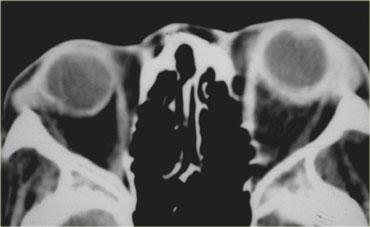

Hình bên trái là hình ảnh của một bệnh nhân nhập cấp cứu với tình trạng sưng nề hốc mắt sau chấn thương.

Bệnh nhân này bị vỡ nhãn cầu, cụ thể là vỡ tiền phòng.

Là các bác sĩ chẩn đoán hình ảnh, chúng ta thường chú ý đến dịch kính khi nghi ngờ vỡ nhãn cầu, nhưng như vậy là chưa đủ.

Lưu ý rằng độ sâu của tiền phòng bị giảm.

Có tình trạng tăng tỷ trọng ở phía trước do xuất huyết tiền phòng (hyphema – máu trong tiền phòng).

Cũng cần lưu ý rằng thủy tinh thể bên phải bị mờ và giảm tỷ trọng nhẹ.

Đây được gọi là đục thủy tinh thể do chấn thương.

Có thể bạn sẽ kỳ vọng thủy tinh thể tăng tỷ trọng hơn, nhưng thực tế thường không phải như vậy.

Hình bên trái là hình ảnh CT của một bệnh nhân bị chấn thương mắt trái.

Hãy phân tích hình ảnh để tìm 5 dấu hiệu trước khi tiếp tục đọc.

Các dấu hiệu bao gồm:

- Tiền phòng nông hơn so với bên phải, gợi ý vỡ nhãn cầu.

- Tỷ trọng trong tiền phòng tăng, gợi ý xuất huyết tiền phòng (hyphema).

- Tỷ trọng của thủy tinh thể giảm, cho thấy bệnh nhân bị đục thủy tinh thể do chấn thương.

- Có vùng tăng tỷ trọng trong buồng dịch kính, gợi ý xuất huyết dịch kính.

- Nhãn cầu dẹt ở mặt sau, cho thấy có vỡ dịch kính kèm theo.

Vỡ nhãn cầu thường gặp nhất ở vị trí tiền phòng.